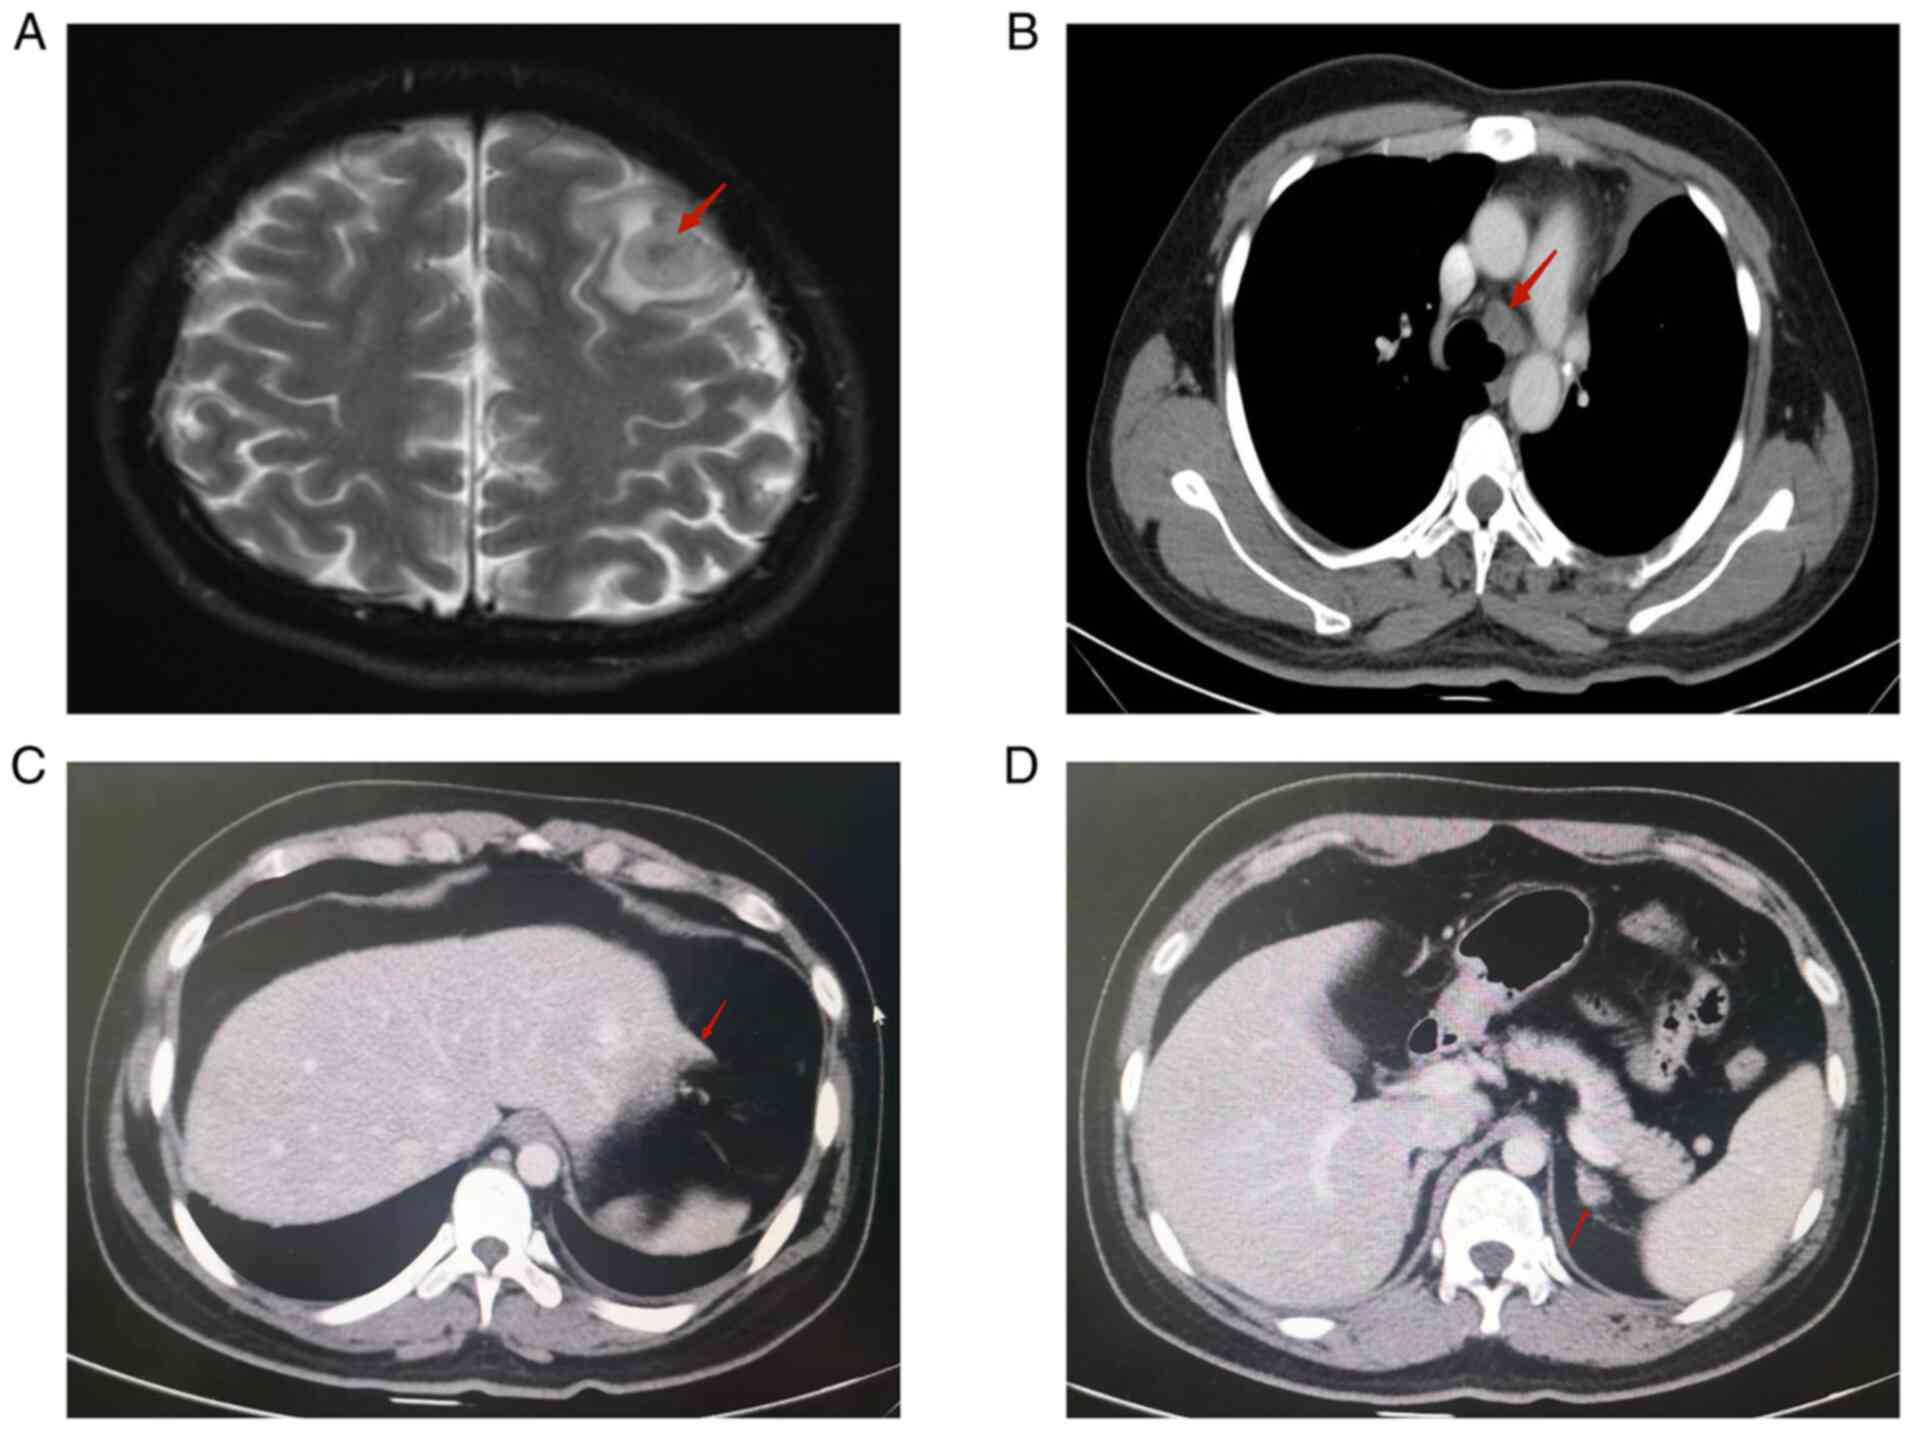

After one month, a tumor specimen from the patient was examined for a pathological consultation at a different hospital, which corroborated our results. Genetic testing using next-generation sequencing revealed no mutations in commonly implicated genes, such as EGFR, BRAF, MET or RAS; however, the sequencing identified an EML4-ALK fusion and further IHC analysis revealed a high degree of PD-L1 expression [tumor proportion score (TPS) >70%] (Fig. 3). Unfortunately, the patient's cancer progressed rapidly and a comprehensive evaluation revealed enlargement of the bilateral hilar and mediastinal intramural lymph nodes. There were also multiple distant metastatic lesions involving the abdominal mesenteric region, the omental region (the largest measuring ~3.4×2.4 cm), the lateral left lobe of the liver and the left adrenal gland (measuring ~1.3×1.0 cm). Furthermore, multiple bilateral metastases, with edema, were discovered in the brain (Fig. 4). These findings led to the diagnosis of postoperative mediastinal lymph node, abdominal, adrenal and brain metastases from the adenocarcinoma of the upper lobe of the left lung combined with sarcomatoid carcinoma (T4N2M1c stage IVB, EML4/ALK fusion, PD-L1 TPS >70%).